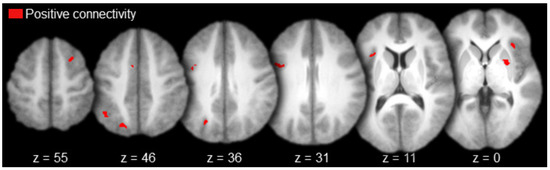

| All participants | |||||

| Positive activations | |||||

| R. Superior Frontal Sulcus | 6/8 | 27 | 12 | 53 | 29 |

| L. Precentral Sulcus | 6 | −37 | 3 | 32 | 48 |

| L. Medial Prefrontal Cortex | 6 | −7 | 8 | 50 | 37 |

| L. Intraparietal Sulcus | 19/39 | −19 | −68 | 45 | 50 |

| L. Intraparietal Sulcus | 7/40 | −39 | −55 | 45 | 27 |

| L. Insula | − | −31 | 16 | 4 | 32 |

| R. Insula | − | 34 | 24 | −2 | 43 |

| R. Putamen | − | 27 | 3 | 0 | 41 |

| Negative activations | |||||

| No activations |